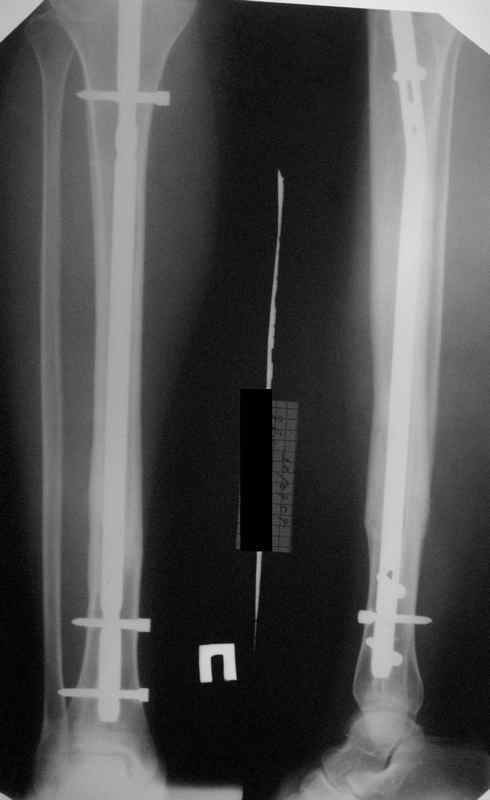

Re: неправильно фиксированный перелом

Вот именно количественный, т.е. сколько градусов в вальгусе допустимо и при каком диастазе в мм или в % от толщины диафиза.

Но почему решение динамизировать на сроке 8 недель с полным удалением всех проксимальных винтов даже не рассматривается Вами? Ведь тогда нагрузка с фиксатора будет снята, и переломов металла можно будет не бояться и наступать полной нагрузкой.

Все это к тому, что те, кто занимается гвоздями и Вы в том числе можете выложить не один снимок с подобными диастазами и вальгусами-варусами, где достигнуто сращение и не получено проблем. Тогда откуда такая "адназначность" врешении об реостеосинтезе?